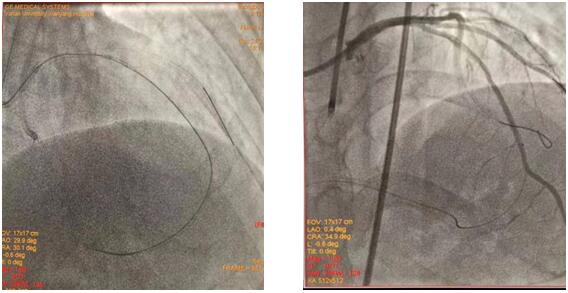

(插图说明:图1为双侧造影图、图2为导丝正向通过图、图3为求那边、图3为球囊通过图、图4为导丝逆向通过图)

在吴栋梁院长的协调安排下,从12月24日清晨7:30到12月25日清晨7:50安全完成62例介入手术。其中,心血管内科二病区介入团队在左梅主任的带领下,清晨七点半开始,C3830电极对于左束支区域起搏、永久起搏器的成功置入,逆向技术开通LAD近段无残端闭塞病变的顺利完成,创造着一个个生命的奇迹,为心血管病患者带来一个不平凡的平安夜。